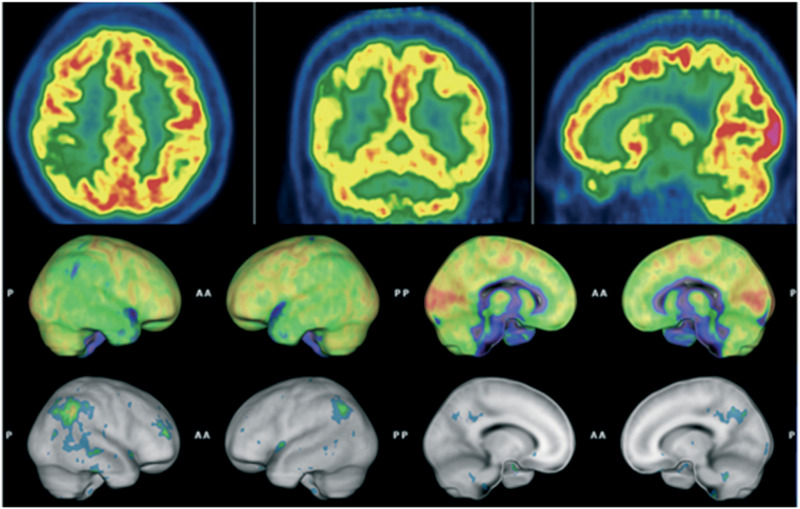

Abstract Image